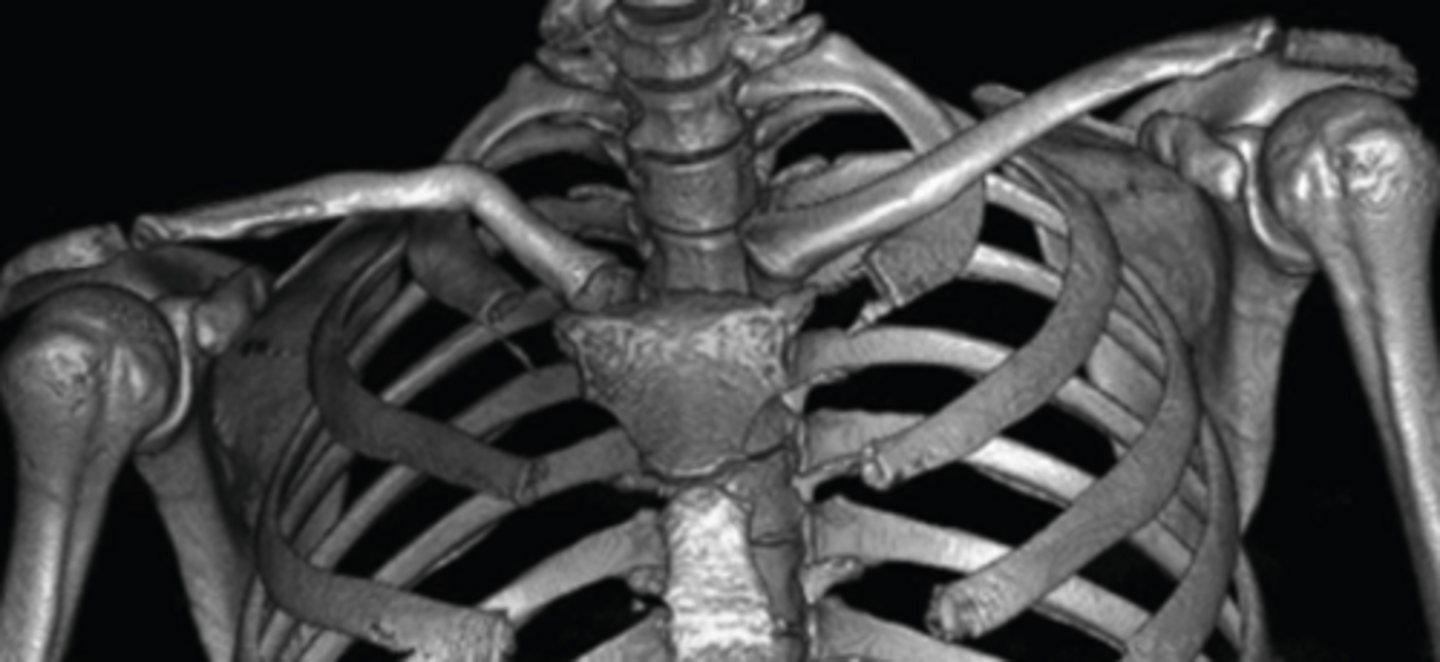

Cervical and chest radiographs to identify cervical ribs, prominent C7 transverse processes, or masses.

What is the role of CT/MRI imaging in TOS?

Evaluate osseous space-occupying lesions, malunited fractures of ribs or clavicle, and soft tissue anatomic anomalies